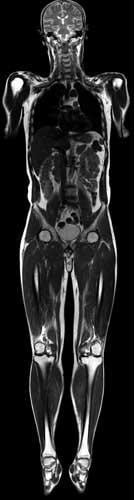

- Whole-body MRI